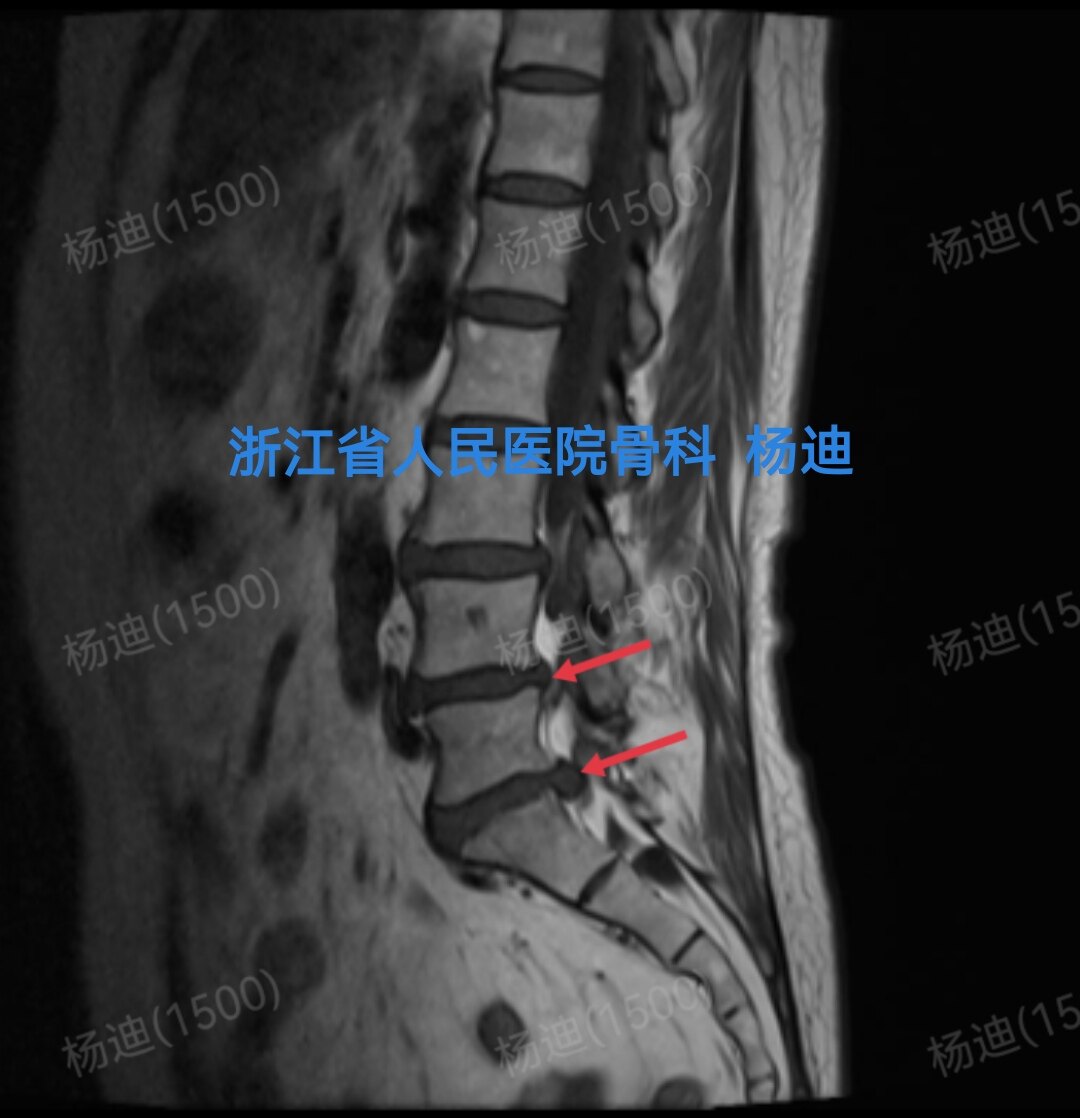

图为腰椎磁共振T2相检查结果,提示腰4/5、腰5/骶1椎间盘突出(红色箭头),硬膜囊受压。

图为腰椎磁共振T2相检查结果,提示腰4/5、腰5/骶1椎间盘突出(红色箭头),硬膜囊受压。

图为腰椎磁共振T1相检查结果,提示腰4/5、腰5/骶1椎间盘突出(红色箭头),硬膜囊受压。

图为腰椎磁共振T1相检查结果,提示腰4/5、腰5/骶1椎间盘突出(红色箭头),硬膜囊受压。